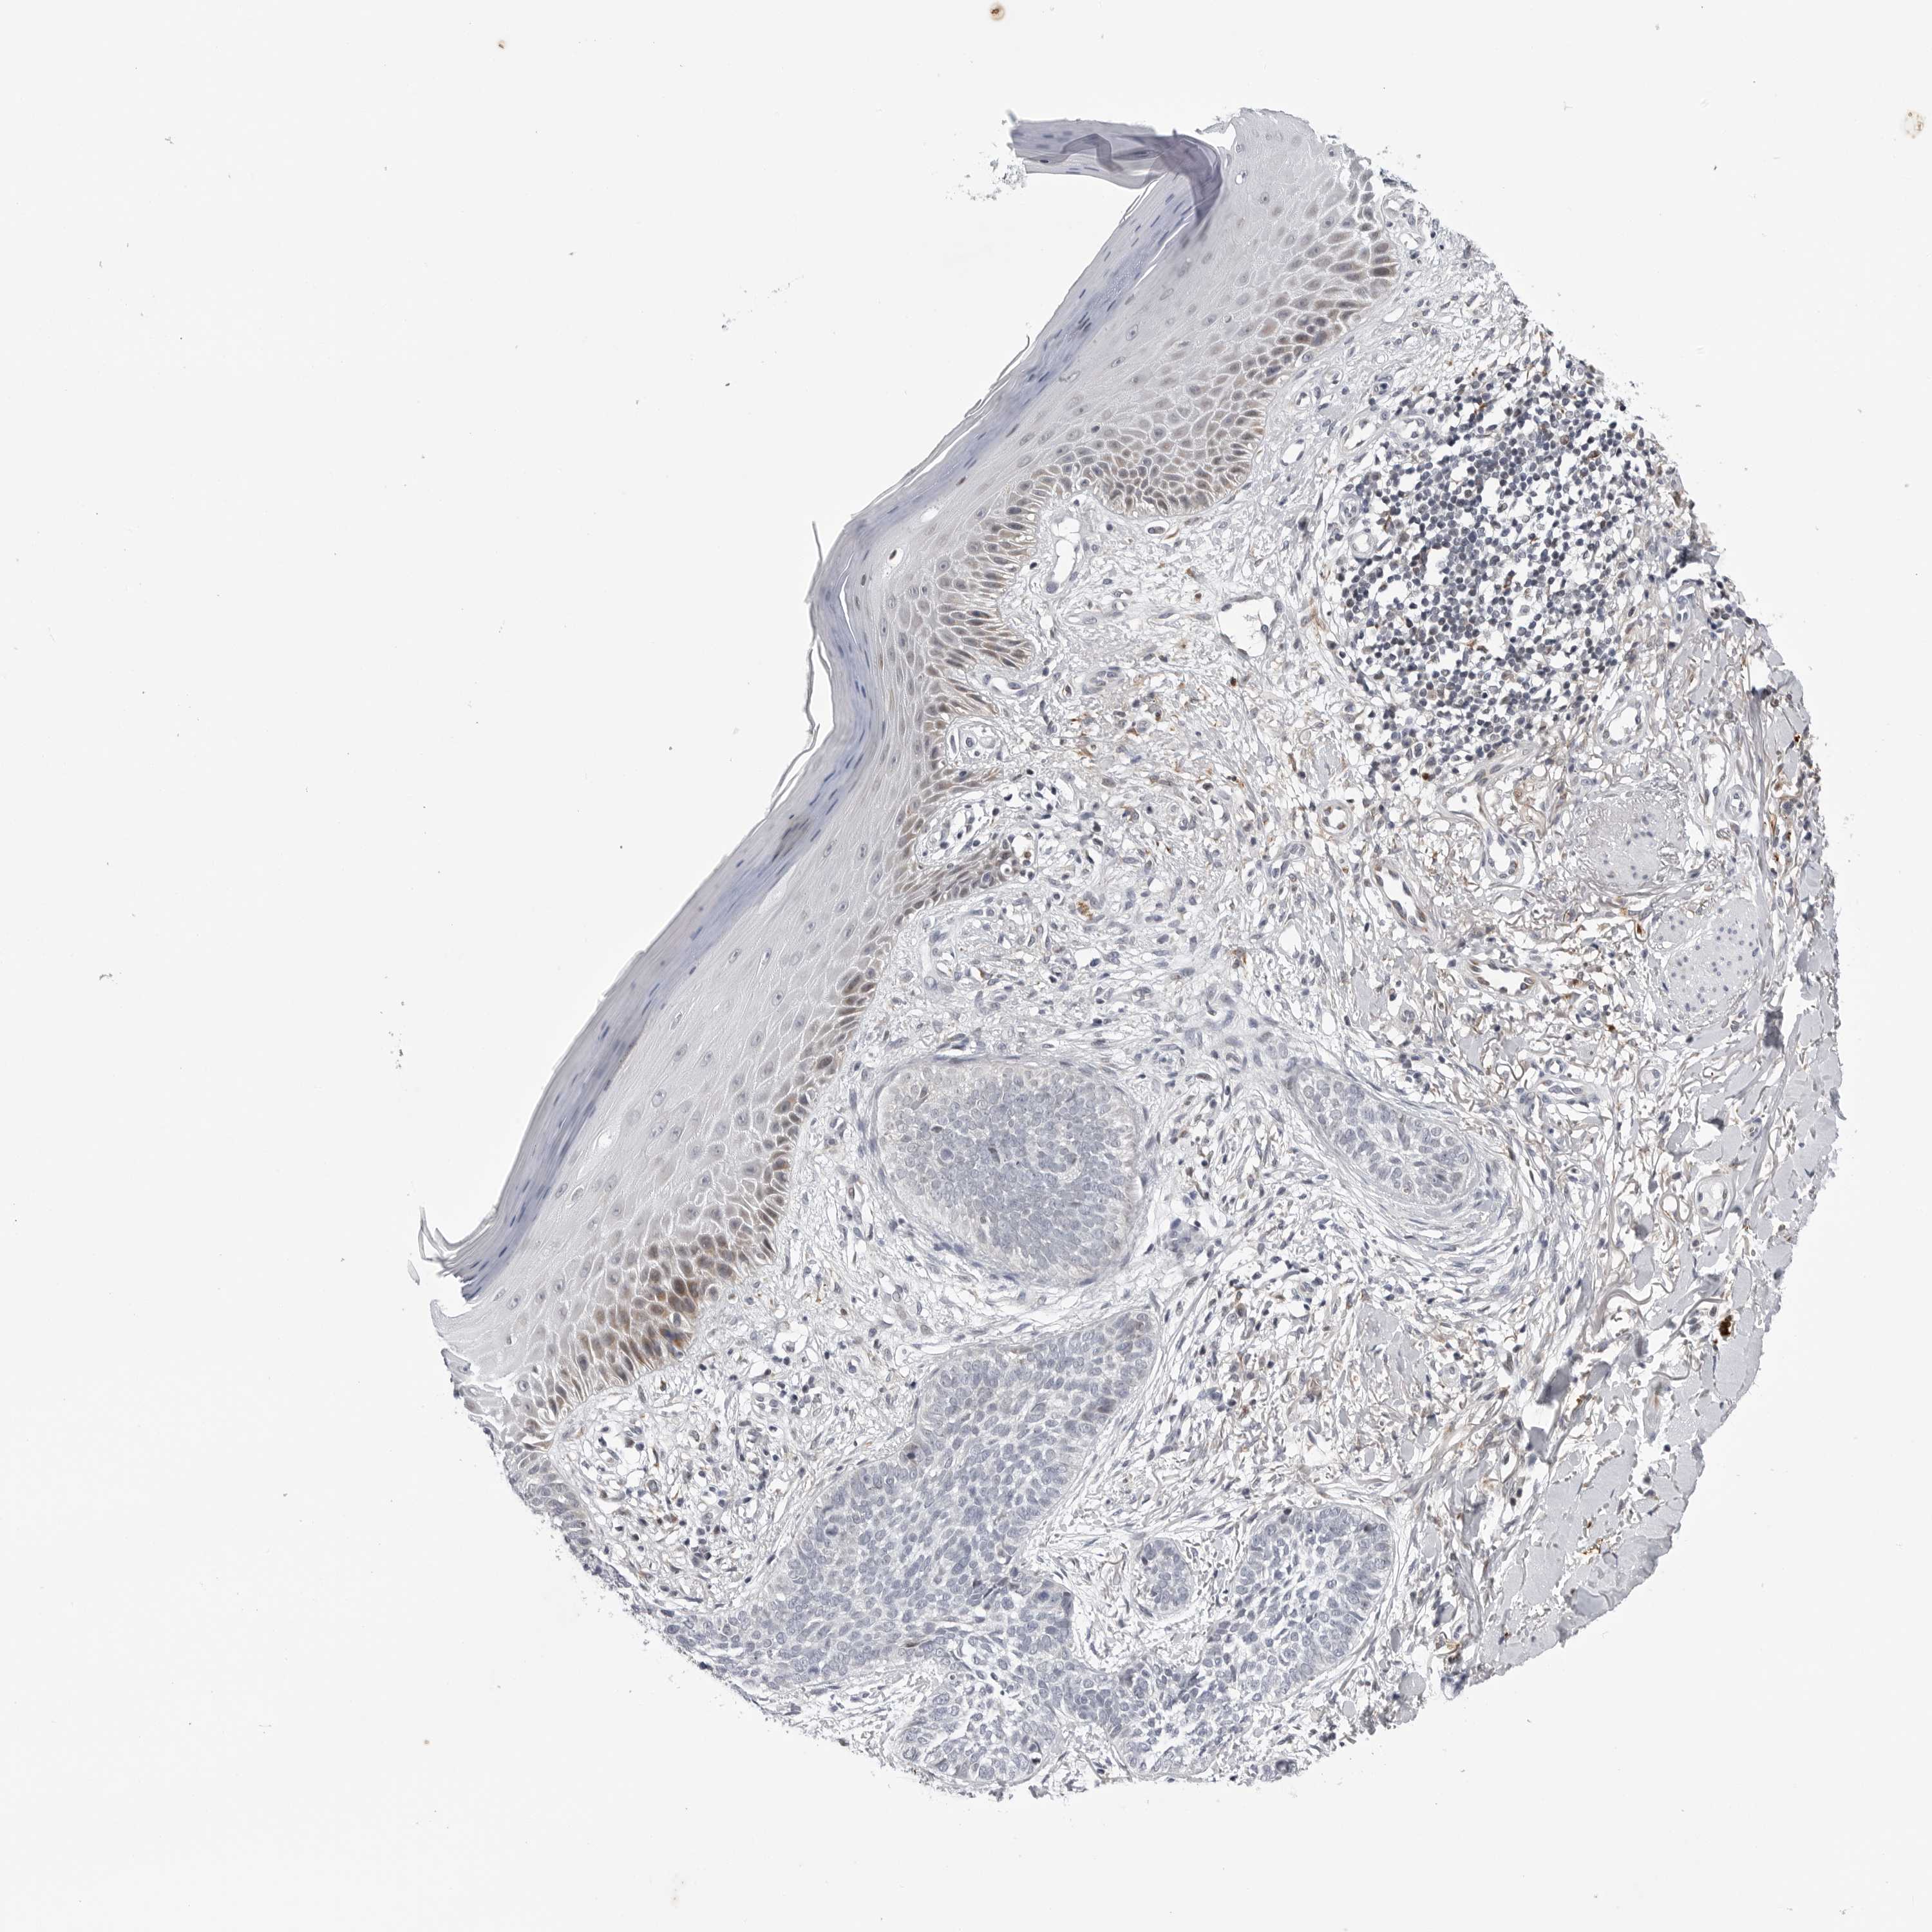

SKIN CANCER - Protein expressioni

A mouse-over function shows sample information and annotation data. Click on an image to view it in a full screen mode. Samples can be filtered based on level of antibody staining by selecting one or several of the following categories: high, medium, low and not detected. The assay and annotation is described here.

Each image is clickable and will lead to virtual microscopy that enables deeper exploration of all samples and also displays staining intensity scores, fraction scores and subcellular localization as well as patient and tissue information for each sample.

Antibody HPA007666

Basal cell carcinoma